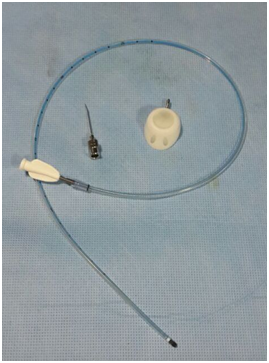

PICC Catheters are made of silicone or polyurethane based material and these PICC can be single lumen, double lumen or triple lumen. PICC are generally long intravenous lines inserted under ultrasound guidance in basilica vein or brachial vein. These PICC are available in sizes from 3 to 7Fr. Rarely PICC are inserted through axillary vein or cephalic vein. It is helpful to place a tourniquet around the upper arm to distend the vein before puncture. The advantage of inserting PICC under image guidance is that PICC can be inserted through mid-arm vein and elbow joint is free for movement. Some IR are these days placing tunnelled PICC for securing these PICC and to decrease change of infection at exit site. The inner end of these PICC is generally at cavoatrial junction. However, it is now standard practice to position the catheter tip in the upper to mid right atrium with the patents supine.2 PICC can be open ended or closed ended (Table 1). Open ended PICC have end hole. Whereas, closed ended PICC have Groshong side valve. Groshong valve allows fluid injection and blood aspiration, but prevents air or blood from entering the catheter, when these catheters are not in use. Groshong tip catheter are usually blue and don’t require clamping or heparin flush. Power PICC have recently been approved for use in India and these PICC can be used with pressure injector with flow rate up to 5ml/sec and pressure up to 300 Psi (Figure 1) (Figure 2).

Figure 1 Open ended single lumen PICC with peel-off sheath and dilator

Figure 2 Single lumen Power PICC with peel-off sheath and dilator